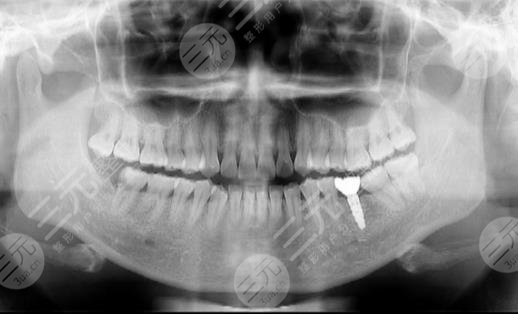

三、长沙中诺口腔医院牙齿种植经历分享

我妈妈今年才45多岁,但是牙齿都出现了问题,经常会出现牙痛的情况,所以就把牙齿拔掉了,但在安装牙齿的时候,一直不知道选择什么样的材质更好,也不知道选择哪家医院更加不错,后来打听之后才知道长沙中诺口腔医院在种植牙齿的时候能够有着独特的见解,而且可以根据个人的经济条件详细的分析。

在安装牙齿的时候,我经过和医生进行沟通之后,建议选择烤瓷牙齿,因为烤瓷牙齿使用的时间长,而且坚硬度也是比较不错的,虽然价格相对较贵,在使用的时候更好一些。

在开始种植牙齿的时候总是感觉不舒适,说吃任何东西都不得劲,不过过了一段时间之后还是挺好的,种植牙齿也没有任何不舒适感,没有造成牙龈肿痛的情况。不然牙齿已经有两个月的时间了,挺不错的,果也很好。吃东西的时候也比较得劲,没有遇到任何牙齿不舒服的现象。所以在种植牙齿的时候,我还是建议大家根据个人的情况选择,医院的口碑确实挺不错的,而且服务态度较为到位,可以放心的选择。